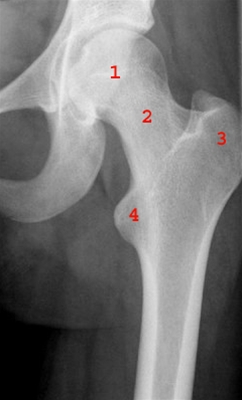

Frontalbillede af venstre hofte.

1. Caput femoris (ledhoved)

2. Collum femoris (lårhals)

3. Trochanter major

4. Trochanter minor